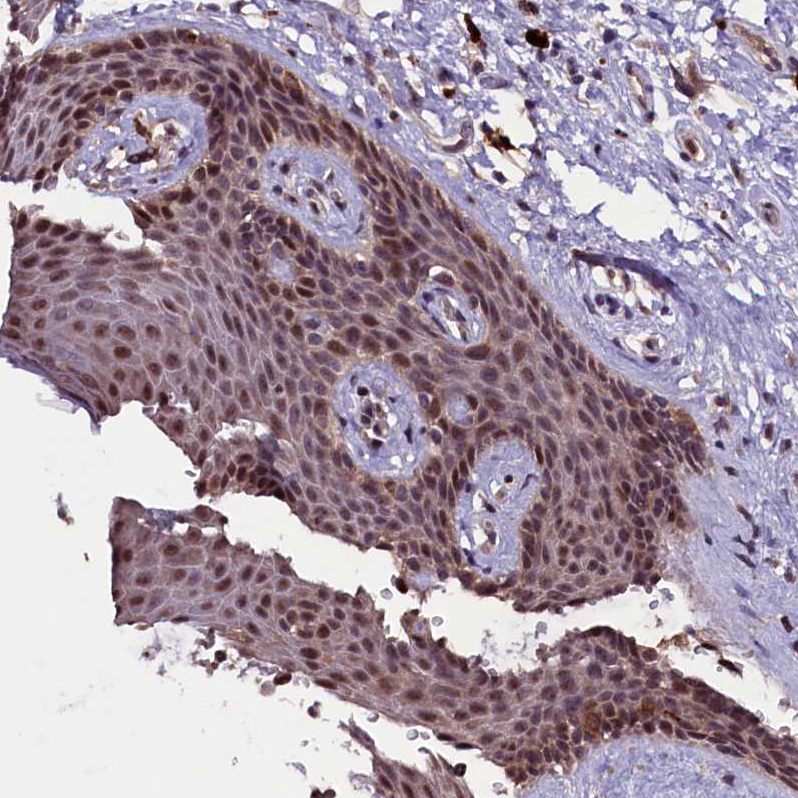

Immunohistochemical staining of human testis shows strong nuclear positivity in cells in seminiferous ducts.